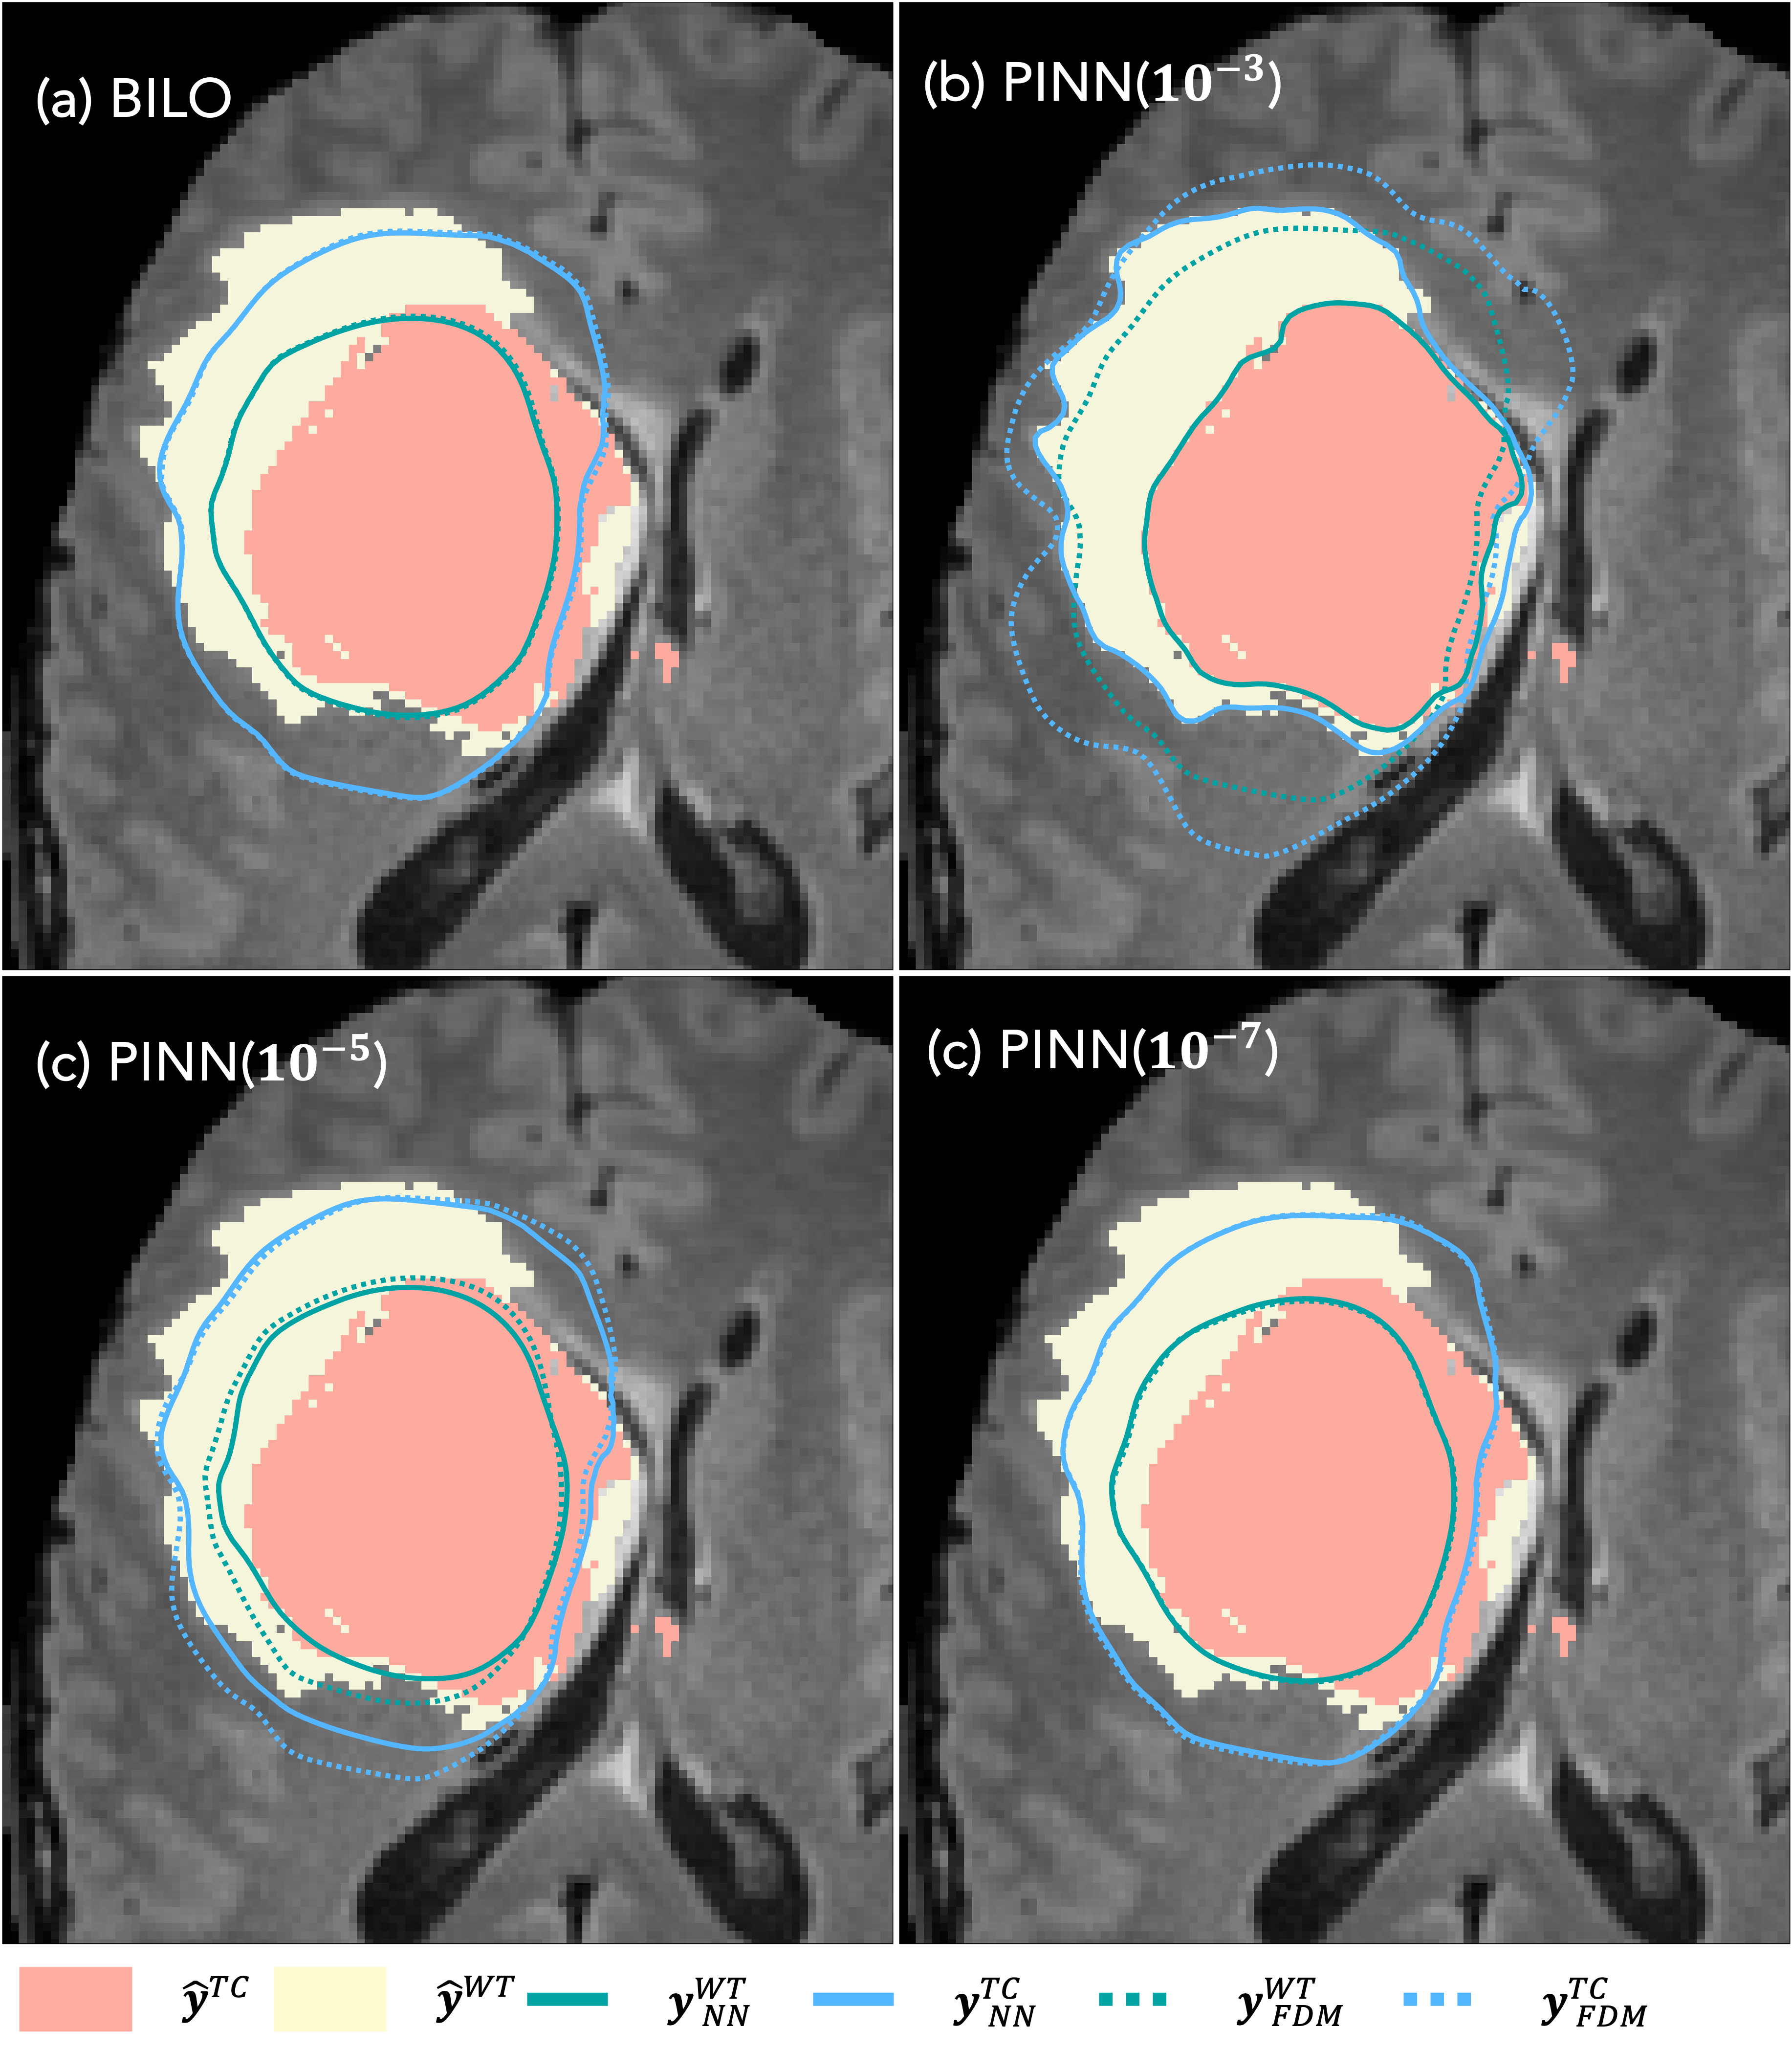

In this inference problem, the ground truth values for the parameters DD, ρ\rho, ucWTu_{c}^{\rm WT}, and ucTCu_{c}^{\rm TC} are not available. Therefore, we evaluate the quality of the inferred parameters by comparing the predicted segmentations 𝐲^\hat{\mathbf{y}} with the observed segmentation 𝐲\mathbf{y} data using the DICE score, which is defined as 2𝐲,𝐲^/(𝐲1+𝐲^1)2\langle\mathbf{y},\hat{\mathbf{y}}\rangle/(\|\mathbf{y}\|_{1}+\|\hat{\mathbf{y}}\|_{1}) [13]. DICE is a standard metric in medical image segmentation that quantifies the overlap between two binary masks [36, 85].

The predicted segmentations are obtained by thresholding the tumor cell density at the inferred thresholds ucWTu_{c}^{WT} and ucTCu_{c}^{TC}. These densities can be computed either from the numerical PDE solution uFDMu_{\rm FDM} or the neural network surrogate uNNu_{\rm NN}, resulting in predicted masks denoted by 𝐲FDMs\mathbf{y}^{s}_{\rm FDM} and 𝐲NNs\mathbf{y}^{s}_{\rm NN}, respectively. We define DICEm\mathrm{DICE}_{m}, m{NN,FDM}m\in\{\text{NN},\text{FDM}\}, as the average DICE score across the WT and TC regions using the corresponding predicted segmentation.

Table 1 reports the relative errors of uNNu_{\rm NN} and uFDMu_{\rm FDM} at t=1t=1, as well as the DICE scores DICEm\mathrm{DICE}_{m}. Figure 15 visualizes the predicted segmentations using BiLO and PINN for different values of wdataw_{\rm data}. For the PINNs, we observe that the DICE score based on uNNu_{\rm NN} is generally higher than that based on uFDMu_{\rm FDM}, indicating a tendency to overfit the data while compromising the fidelity of the PDE solution. This behavior is reflected in the larger relative errors of uNNu_{\rm NN} and is visually apparent in Figure 15, where the contours from uNNu_{\rm NN} track the noisy segmentation data more closely than those from uFDMu_{\rm FDM}.

Reducing wdataw_{\rm data} helps mitigate this overfitting by regularizing the data fitting. In contrast, BiLO achieves both accurate PDE solutions and well-performing parameters without the need to tune wdataw_{\rm data}, leading to better segmentations in this case. Interestingly, even when uNNu_{\rm NN} is not accurate in the PINN setting, the inferred parameters can still yield reasonable segmentation when evaluated using uFDMu_{\rm FDM}, as evidenced by the corresponding DICE scores.

Table 1: Results of the GBM inverse problem: Average DICE scores for the WT and TC regions based on predicted segmentations from the neural network solution uNNu_{\rm NN} and the numerical solution uFDMu_{\rm FDM}, along with the relative mean squared error (MSE) of uNNu_{\rm NN} at t=1t=1

Methods DICENN\rm DICE_{NN} DICEFDM\rm DICE_{FDM} rel.MSE(%)\rm rel.MSE(\%)

BiLO 0.84 0.84 0.04

PINN(10310^{-3}) 0.98 0.75 28

PINN(10510^{-5}) 0.87 0.83 1

PINN(10710^{-7}) 0.83 0.83 0.03

Refer to caption

Figure 15: Predicted segmentation using PINN with wdataw_{\rm data} = 10310^{-3}, 10510^{-5}, 10710^{-7} and BiLO. The solid and dashed contours are the predicted segmentation based on uNNu_{\rm NN} and uFDMu_{\rm FDM}. BiLO gives almost overlapping contours, suggesting high accuracy of uNNu_{\rm NN}.